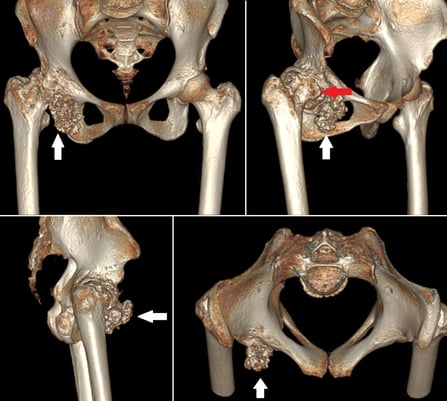

Inverted horn myositis ossificans circumscripta in the pelvis and bilateral adductors

Myositis ossificans is a benign ossifying lesion which can affect any soft tissue including subcutaneous fat, tendons, muscles and nerves. The common locations include the elbow, hip and knee. The pelvis is an extremely rare site for myositis ossificans which has only been described anecdotally in the past. Myositis ossificans involving the adductor muscles- adductor longus or adductor magnus is also an uncommon location, with only a few case reports of its occurrence in athletes. Myositis ossificans involving the adductor longus has been reported to occur in the form of a long, slender, pencil shaped ossification, however the inverted horn is being reported for the first time.